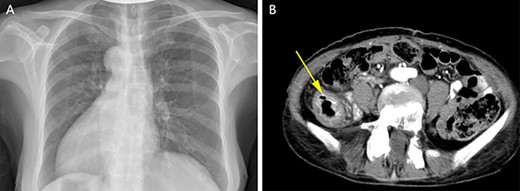

A physical examination revealed that the abdomen is flat, without gastrointestinal type and peristaltic wave, and the right lower abdomen has mild tenderness, with no rebound pain and muscle tension, and the mass can not be touched. Serum tumor markers were not elevated (CEA 2.3 ng/ml and CA-199 4.15 ng/ml). The laboratory examination confirmed mild anemia and hypoproteinemia. Abdominal computerized tomography (CT) showed the apex of the heart on the right side, the liver on the left side of the abdominal cavity (Fig. 1A), the stomach and spleen on the right side of the abdominal cavity (Fig. 1B), confirming SIT. In addition, the chest X-ray confirmed the apex of the heart on the right chest (Fig. 2A), and abdominal CT indicated that the tumor (stage T4N0M0) was located in the descending colon (Fig. 2B).

Chest X-ray showed that the heart was on the right side of the chest (A). Enhanced CT of the lower abdomen showed thickening of the descending colon with stenosis and enhancement, which suggested that it might be a tumor of the descending colon (B, yellow arrow).